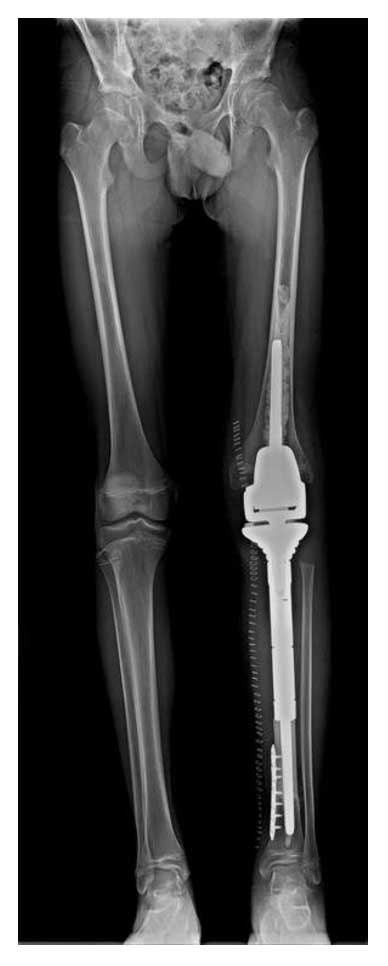

Ameliyat Sonrası: Röntgende rezeksiyon sonrası geri kazanılmış kemik ile proksimal tibia tümör protezi rekonstrüksiyon işlemi görülmekte.